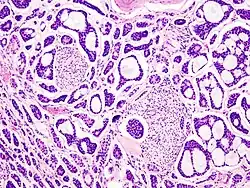

Drei Jahre nach der Erstbeschreibung der Tumorentität durch Robin und Laboulbene[13] prägte der Chirurg Theodor Billroth 1856 zunächst den Begriff Zylindrom,[14] der auf die histologisch erkennbare, zylindrische, von Tumorzellen umsäumte Bindegewebsformationen innerhalb des Tumorgewebes anspielt. Hiervon zu unterscheiden ist heute das dermale Zylindrom, ein gutartiger Tumor der Hautanhangsgebilde.[15][16] Die Bezeichnung adenoid-zystisches Karzinom wurde erstmals vom Pathologen James Ewing benutzt[17] und bezieht sich auf das typische feingewebliche Erscheinungsbild des Tumors, der drüsenartige (adenoide) und teils weite, von Epithel ausgekleidete (zystische) oder auch nicht epithelial ausgekleidete (pseudozystische) Hohlräume ausbildet. Allgemein gebräuchlich wurde der Begriff mit der Aufnahme in die WHO-Klassifikation 1972 nach Vorschlag von Thackray und Sorbin.[18]

Adenoid-zystische Karzinome erscheinen makroskopisch als solide, gut umschriebene, jedoch ungekapselte Tumoren von hellbräunlicher Farbe und variabler Größe. Feingeweblich setzt sich der Tumor aus duktalen und modifizierten myoepithelialen Zellen zusammen, die tubuläre, kribriforme und solide Wachstumsmuster ausbilden. Der Tumor wächst stets infiltrativ in das umgebende Gewebe ein und breitet sich dabei insbesondere entlang von Nervenstrukturen aus (perineurale Invasion).[16]